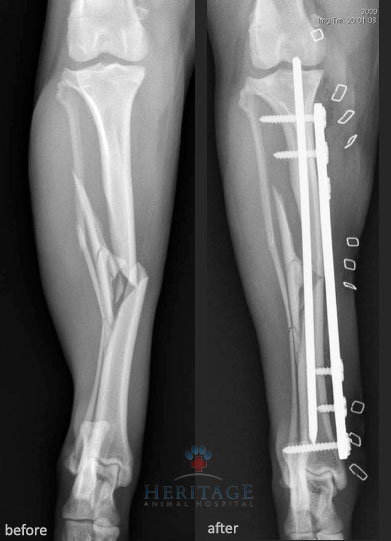

- Fractures — when hit by a car or other accidents